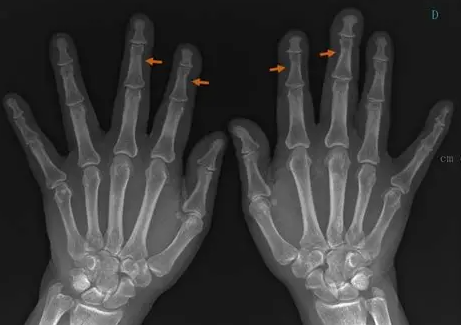

Sarcoidosis

• Lace-like/honeycomb appearance of the fingers

Hyperparathyroidism

• Subperiosteal resorption along radial aspect of phalanges

• Subperiosteal reaction is basically resorption of bone under the periosteum and really looks like subtle inward curve (concave) appearance on the affected side, not very obviously unless very asymmetric on each side

• Acro-osteolysis